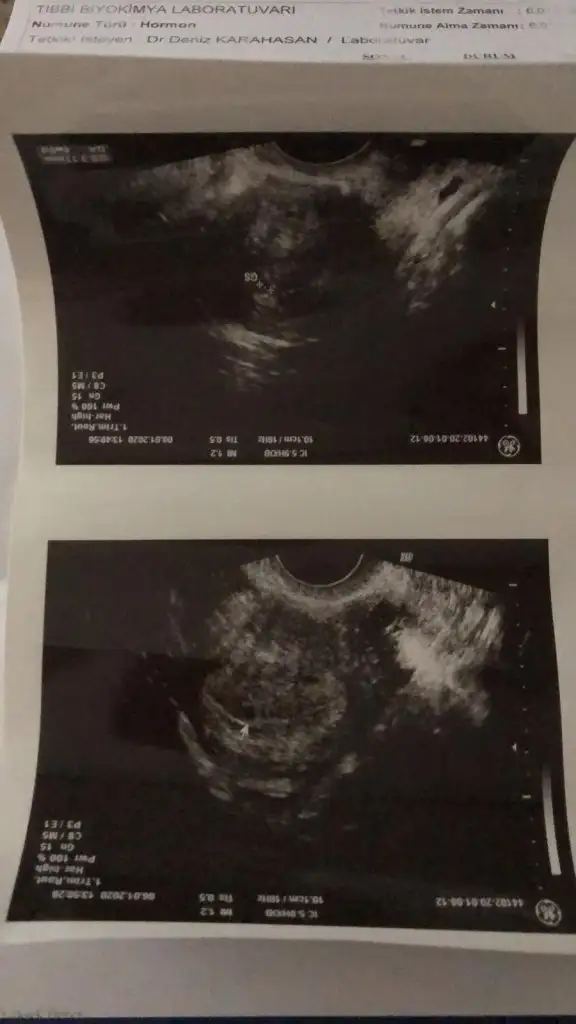

canım gördüğünde tam olarak ne kadarlık hamileydin ben tam 5 hafta 1,11 cm benimki baya küçük sankibende gördüm pazartesi günü keseyi haftaya perşembe bir daha çağırdı riskli gebelik grubundayım ben sıkı takip o yüzden 10,1 cm kese boyutum gayet normal dedi haftasıyla uyumlu yerleşim yeri güzel şekli güzel dedi sabırla bekleyeceğiz dedi 6. gebeliğim bakalım hayırlısı inşaallah

Kesemiz bu canmMaşallah arkadaşım cinsiyet tahmini yapıyor da yuvarlaksa erkek fasulye gibi ise kızmış